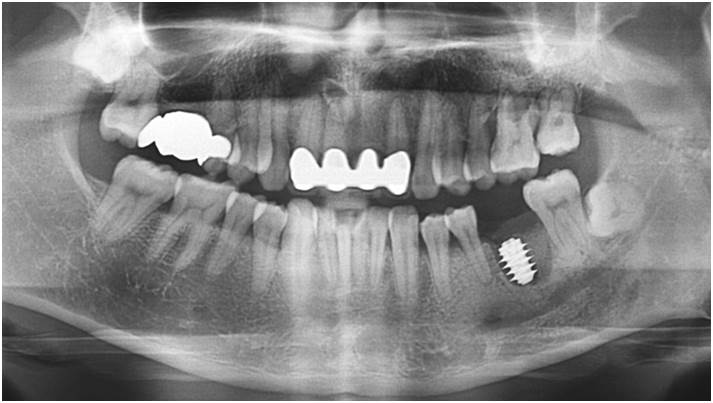

“AnyRidge implant enables fast and stable

osseointegration at this extreme case of bone defect. ”

Clinical case: Bone filling into the bottom of deepest thread at 8.0mm AnyRidge fixture

- Courtesy of Dr. Kwang Bum Park -

Keywords

AnyRidge, Knifethread ,extraction socket, ,initial stability ,Allograft, ,osseointegratio ,Dr. Kwang Bum Park, , Mandibular, Single replacement, AnyRidge, Mega-oss,

Products used

Implant system-AnyRidge, Regeneration-Mega-Oss